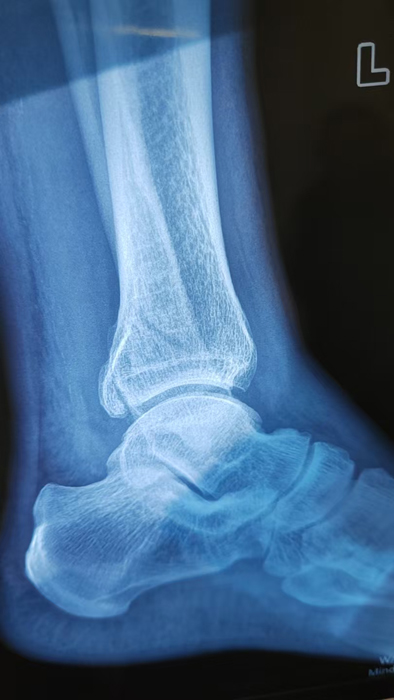

2月4日,何店镇中心卫生院接诊一名左踝关节外伤患者,经影像检查,确诊为左胫、腓骨下段骨折。外科医生姜稳迅速完成术前检查及病情评估,并与患者及家属深入沟通治疗方案。在患者强烈要求于本院进行手术的情况下,为最大限度保障手术质量与安全,该院特邀请医共体牵头单位——曾都区人民医院脊柱创伤外科专家团队前来指导。